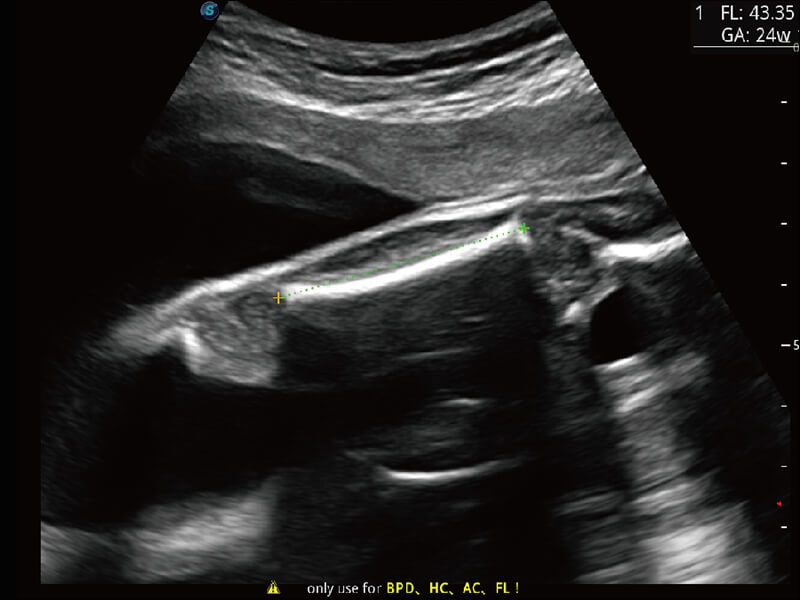

S-Fetus 产科扫查助手

• 缩短

操作时间

• 提升

准确率

• 单次

按键操作